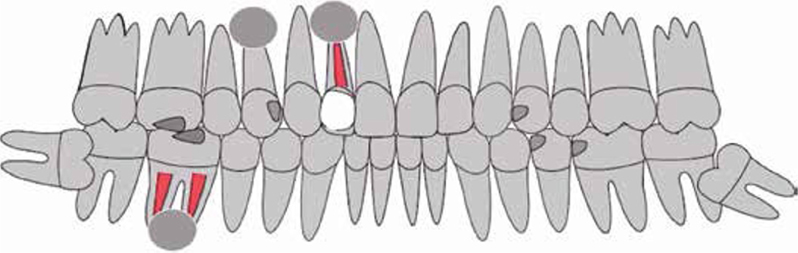

Afb. 7

Grafische weergave van de status praesens bij de intake.

Afbeelding vergroten

Bij het extraoraal onderzoek zie ik een lichte hypertrofie van de m. masseter. Intraoraal tref ik een ernstig versleten dentitie aan waarbij de slijtage niet passend bij de leeftijd kan worden genoemd (afbeelding 2-7 en tabel 1) .